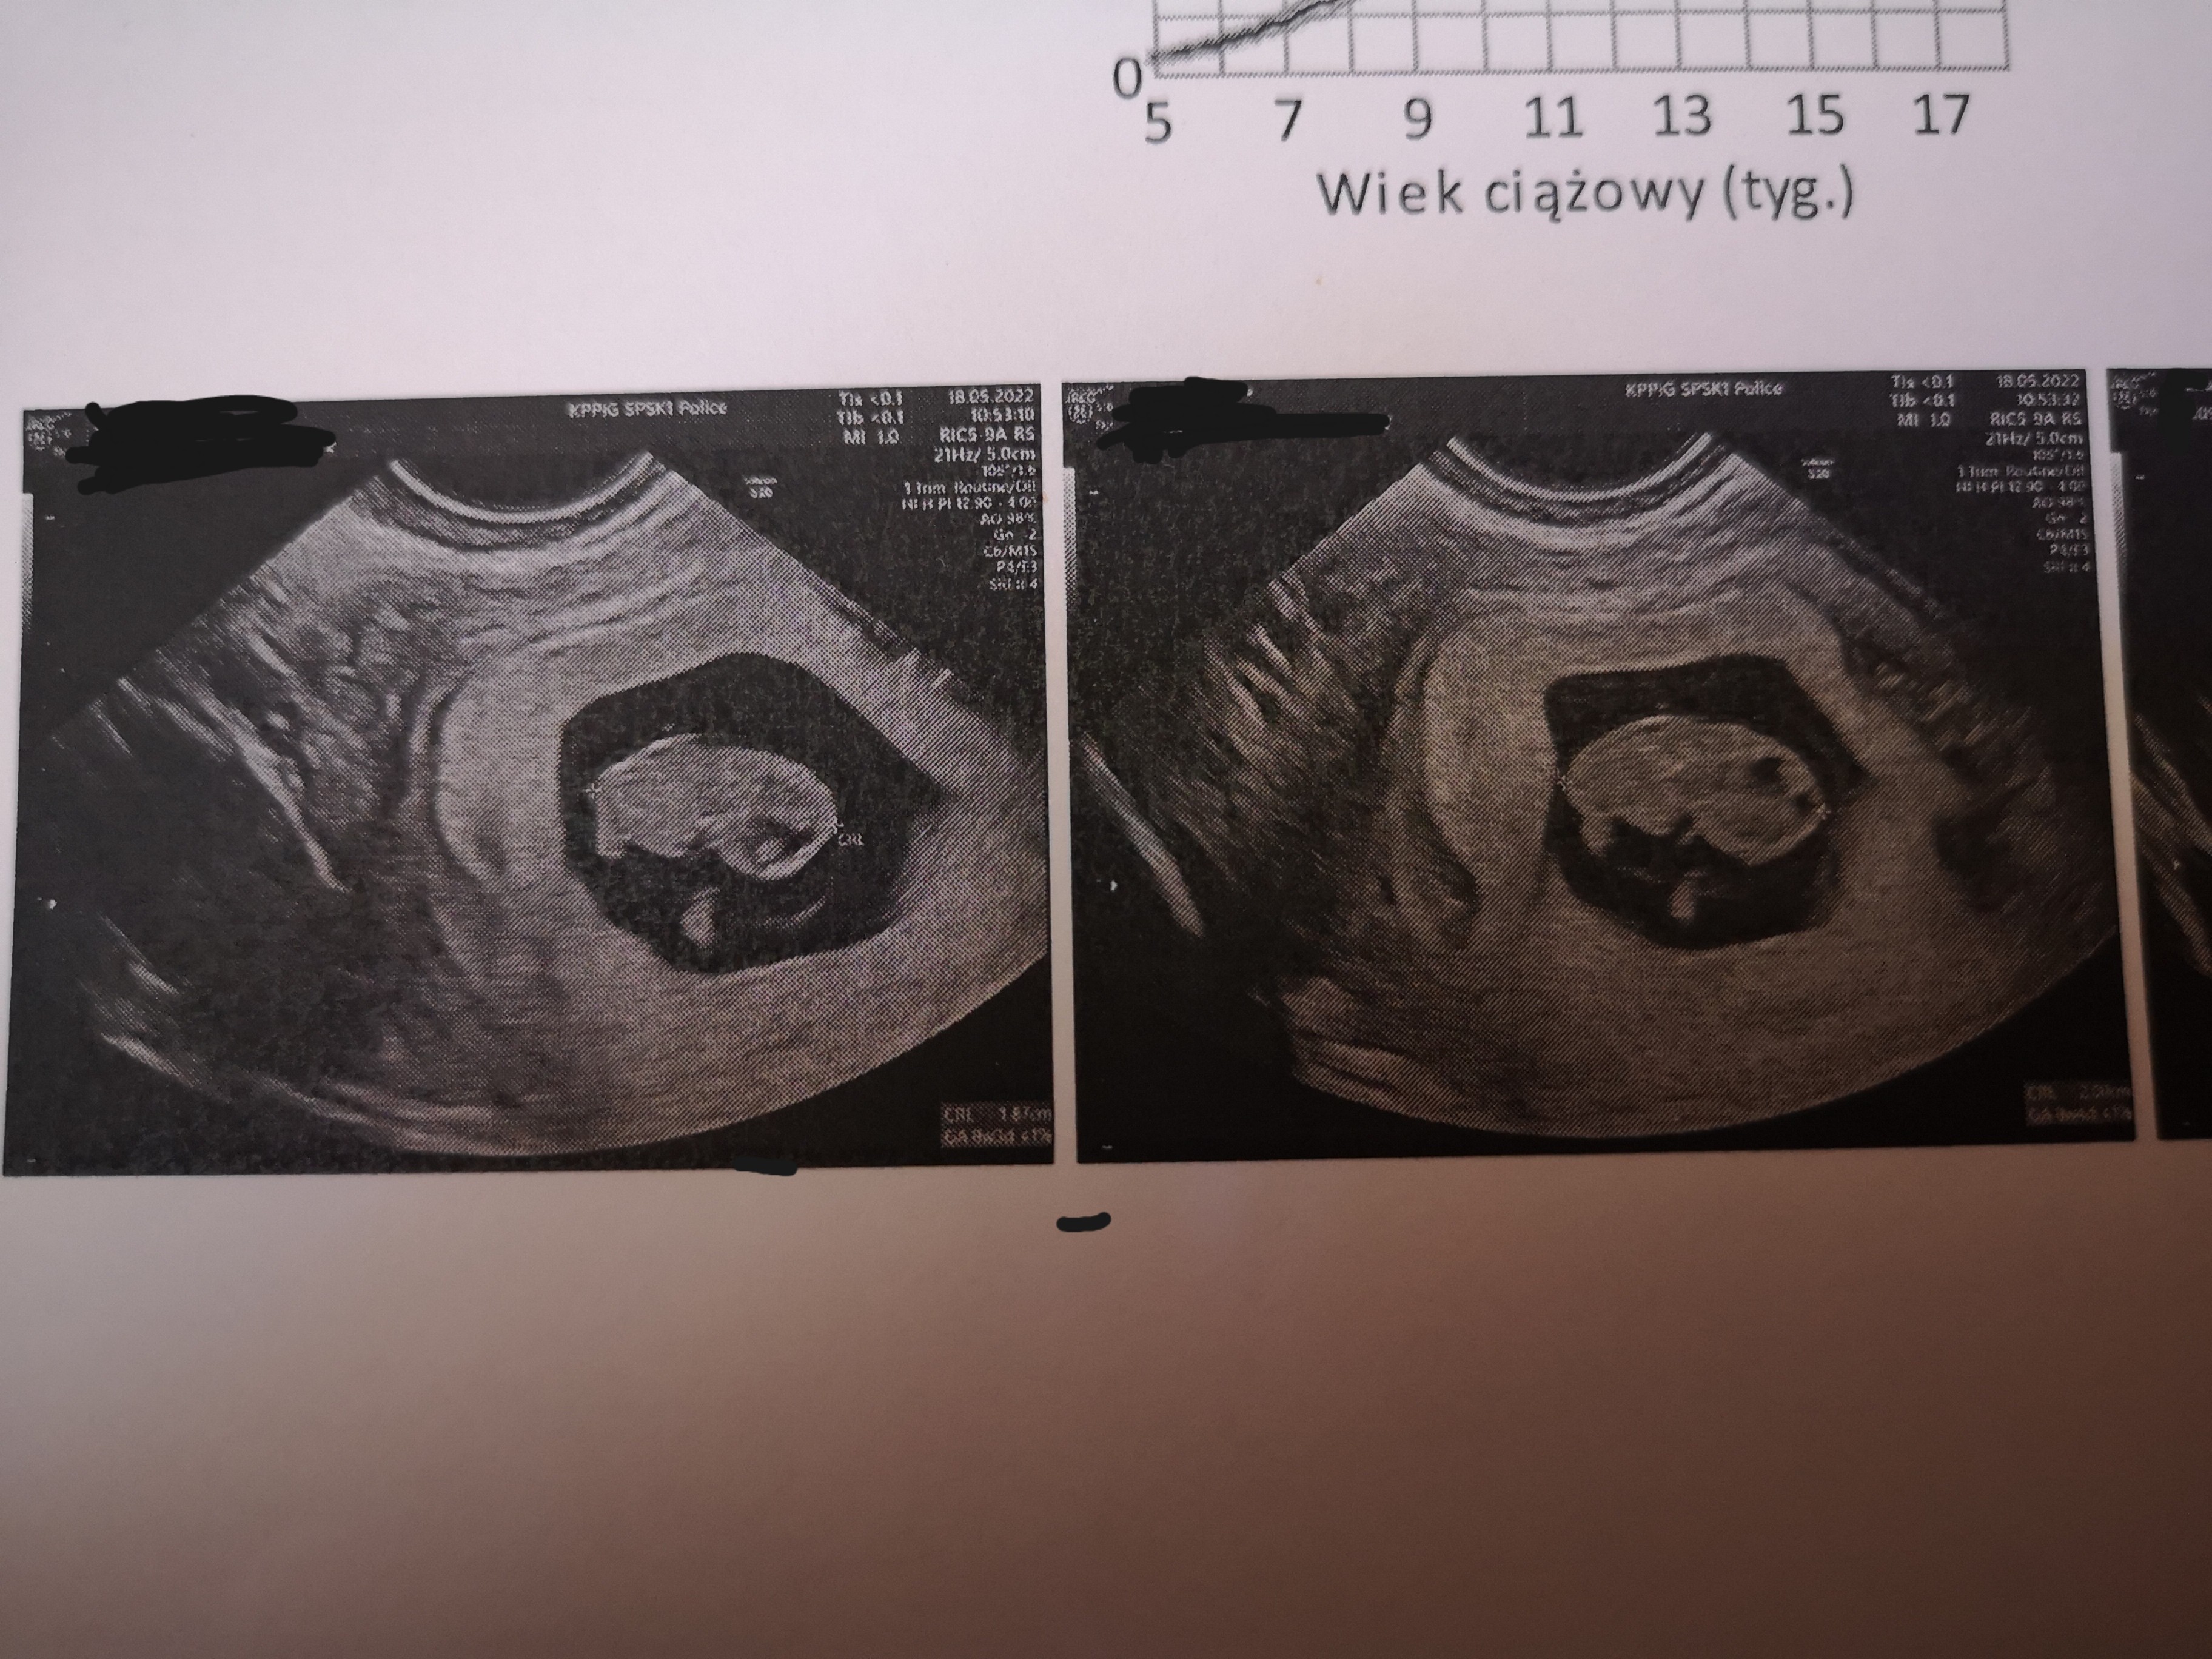

Dziewczyny, wszystko dobrze, maluch ma 38mm i serducho bije. Tyle się dowiedziałam. Ale nigdy więcej ginekologów na NFZ. Nigdy. Weszłam do gabinetu z wynikami morfologii i moczu, lekarz zajrzał do nich, zobaczył że jest ok i na tym chciał skończyć wizytę... Pytam czy możemy zrobić USG, bo zależy mi, żeby poznać aktualną wielkość malucha. Westchnął, przewrócił oczami i zgodził się z wielkim dąsem. Próbował przez powłoki brzuszne, bardzo słabo było widać i wyobraźcie sobie, że powiedział mi - nie no, coś na pewno jest nie tak. Serce mi stanęło!!!

Zrobił dopochwowo i nagle wszystko jest ok. Powiedział, że maluch ma te niespełna 4 cm, posłuchaliśmy przez sekundę serduszka, wyciągnął USG i wyszedł z gabinetu. Zostawił mnie tak o, bez słowa. A na koniec jak poprosiłam o zaświadczenie o ciąży to policzył sobie za nie 50 zł. Wyszłam z przychodni i od razu zadzwoniłam do lekarza, którego bardzo polecają w mojej okolicy. Trudno, będę jeździć 50km i będę tam chodzić prywatnie, ale nie dam sobą tak pomiatać i tak się straszyć